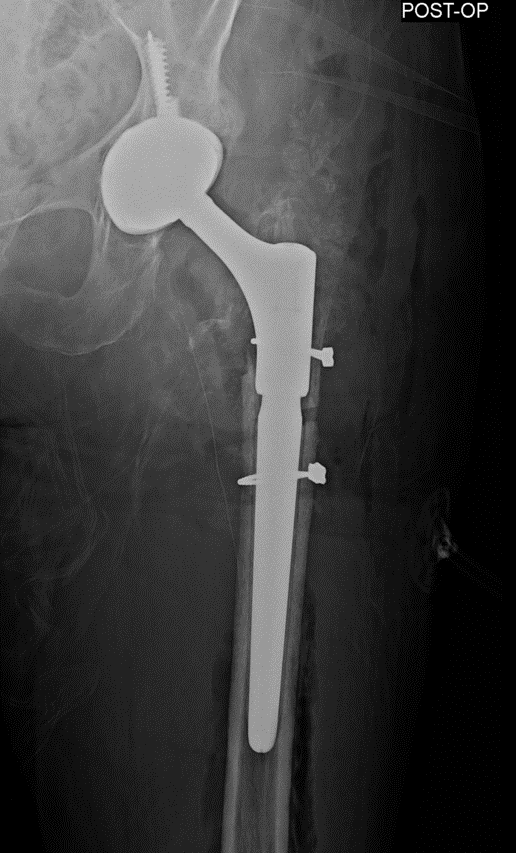

Case presentation: 70 yo F presents to clinic s/p short CMN of left intertroch fx at outside facility in Aug 2022 with worsening left hip pain, inability to bear weight. No pertinent PMHx. Workup and treatment plan?

ETO was performed 15cm in length, Cables were deeply imbedded in bone and had to be cut through with ETO, trephine over the remaining distal stem. Revised to modular fluted tapered stem.

Infxn workup negative, Lateral approach used, Wagner osteotomy to facilitate nail removal, autograft from femoral/neck 50 cc allograft to graft defect in posterior column, multihole cup/screws w/ dual mobility, modular fluted tapered stem.